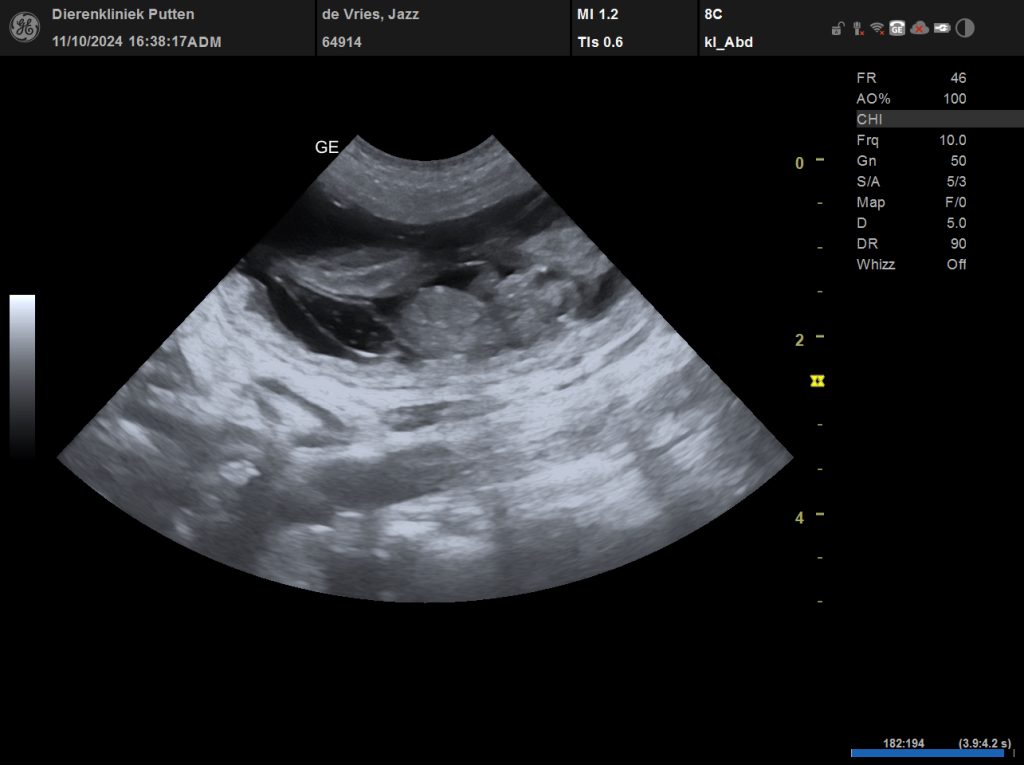

Pups verwacht van Jazz en Funny Rond 12 november verwachten we pups van Internationaal Kampioen Pepper (Jazz) en Splinterhill’s Funny Flintstone (Funny) Jazz Funny